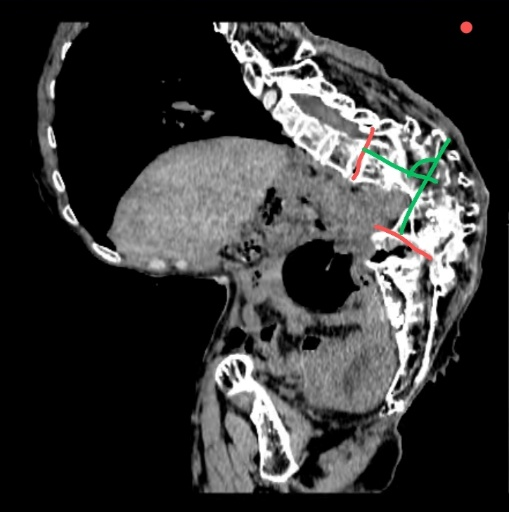

患者因“绝经后阴道流血10天,诊刮病理提示子宫内膜样腺癌”入院。该患者其幼年曾患结核,导致严重脊柱后凸侧弯(俗称“罗锅”),无法平卧,手术时仅能耐受接近坐位的特殊体位,这导致手术操作空间严重受限、暴露困难,术中极易损伤脊柱脊髓,术后拔管困难与低氧血症风险高,加之患者先天性聋哑,医患沟通存在障碍,手术难度与风险极高。

针对患者的复杂病情,在妇科副主任兼奥体院区妇科主任刘鸣的指导下,副主任医师耿锋带领团队联合麻醉与围术期医学科、重症医学科进行了多学科协作攻关,制定了详尽的手术方案,就手术体位、手术路径、切口选择、手术范围、术中突发状况应急处理以及术后生命体征监测等环节均进行了充分讨论与周密准备。子宫内膜癌的标准术式是筋膜外全子宫切除术+双侧附件切除术+前哨淋巴结活检/系统性淋巴结清扫,鉴于该例患者手术体位摆放极其困难及盆腹腔内操作空间极为有限,团队最终决定实施经腹子宫次全切术。手术由耿锋副主任医师主刀,主治医师张硕、住院医师曹烨担任助手。在麻醉与围术期医学科副主任徐艳冰、副主任医师杨淼、住院医师晁慧玲的精准评估与麻醉下,巡回护士徐雯、许彩燕、李英英、李倩对手术体位恰当摆放,器械护士崔瑞言密切配合,手术团队凭借丰富的临床经验和精湛的操作技巧,在极有限的空间内顺利完成子宫次全切术。患者术后转入重症医学科,在重症医学科副主任医师王启志等医护人员的严密监护下,患者顺利拔除气管插管,术后第1天转回妇科病房。通过给予扩张支气管、化痰等措施,患者克服了低氧血症,术后恢复良好,已顺利出院。